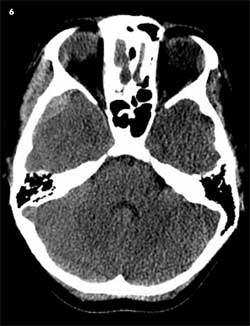

A 16-year-old girl was riding as a passenger on an adult-sized ATV without a helmet when her boyfriend lost control and the ATV rolled over. She sustained a closed head injury, multiple bruises, abrasions, and contusions. A right temporal skull fracture and right temporal fossa epidural hematoma were diagnosed (Figure 6).

The patient was treated with close monitoring of the skull fracture and hematomas. She was admitted for 4 days and had follow-up with physical medicine because of the head injury. She will see the neurosurgeon for serial rechecks and scans. She will continue to be monitored closely for her traumatic brain injury because of some memory difficulties, and she will need therapy for an indefinite period.